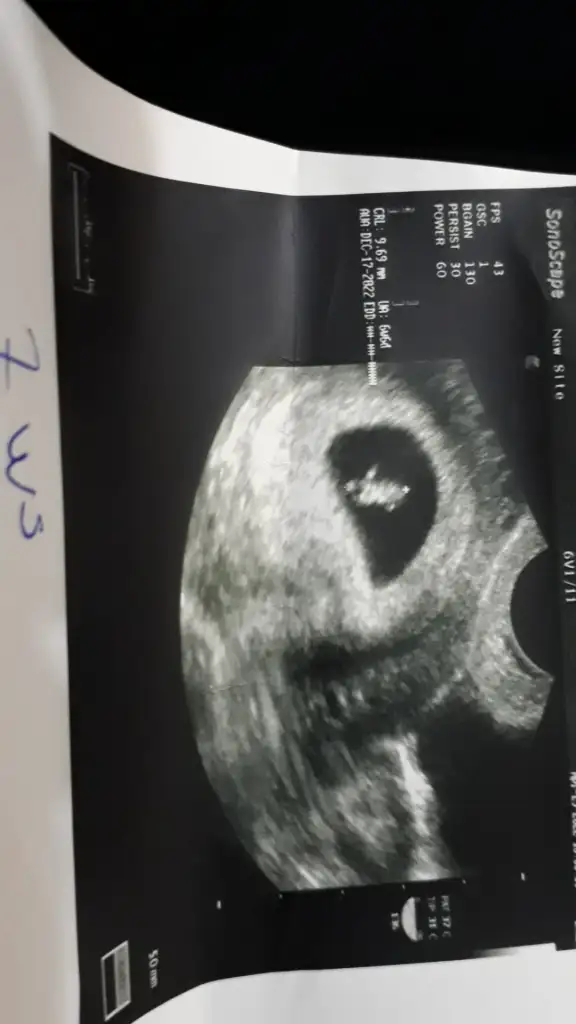

• IMG_20220506_0001.webp

IMG_20220506_0001.webp

22,7 KB · Görüntüleme: 75

9 hafta karından ultrason bana da bakabilir misiniz :)